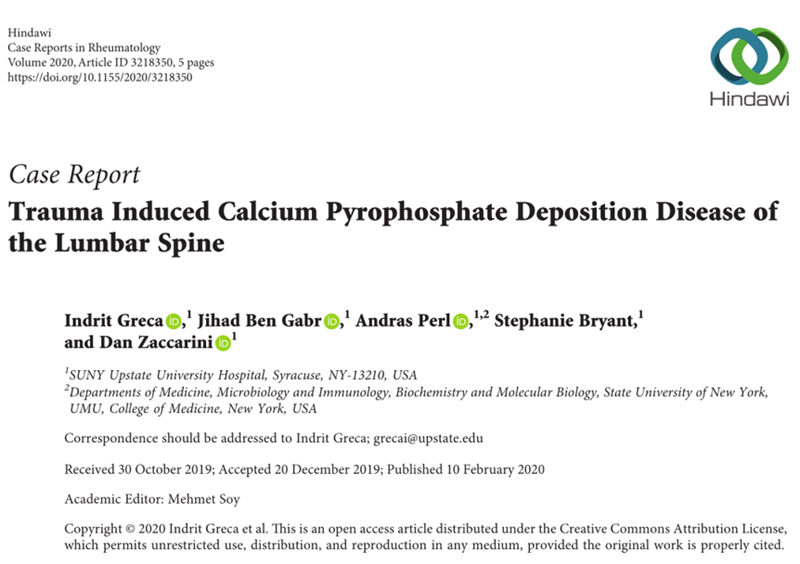

创伤引起的腰椎焦磷酸钙沉积病